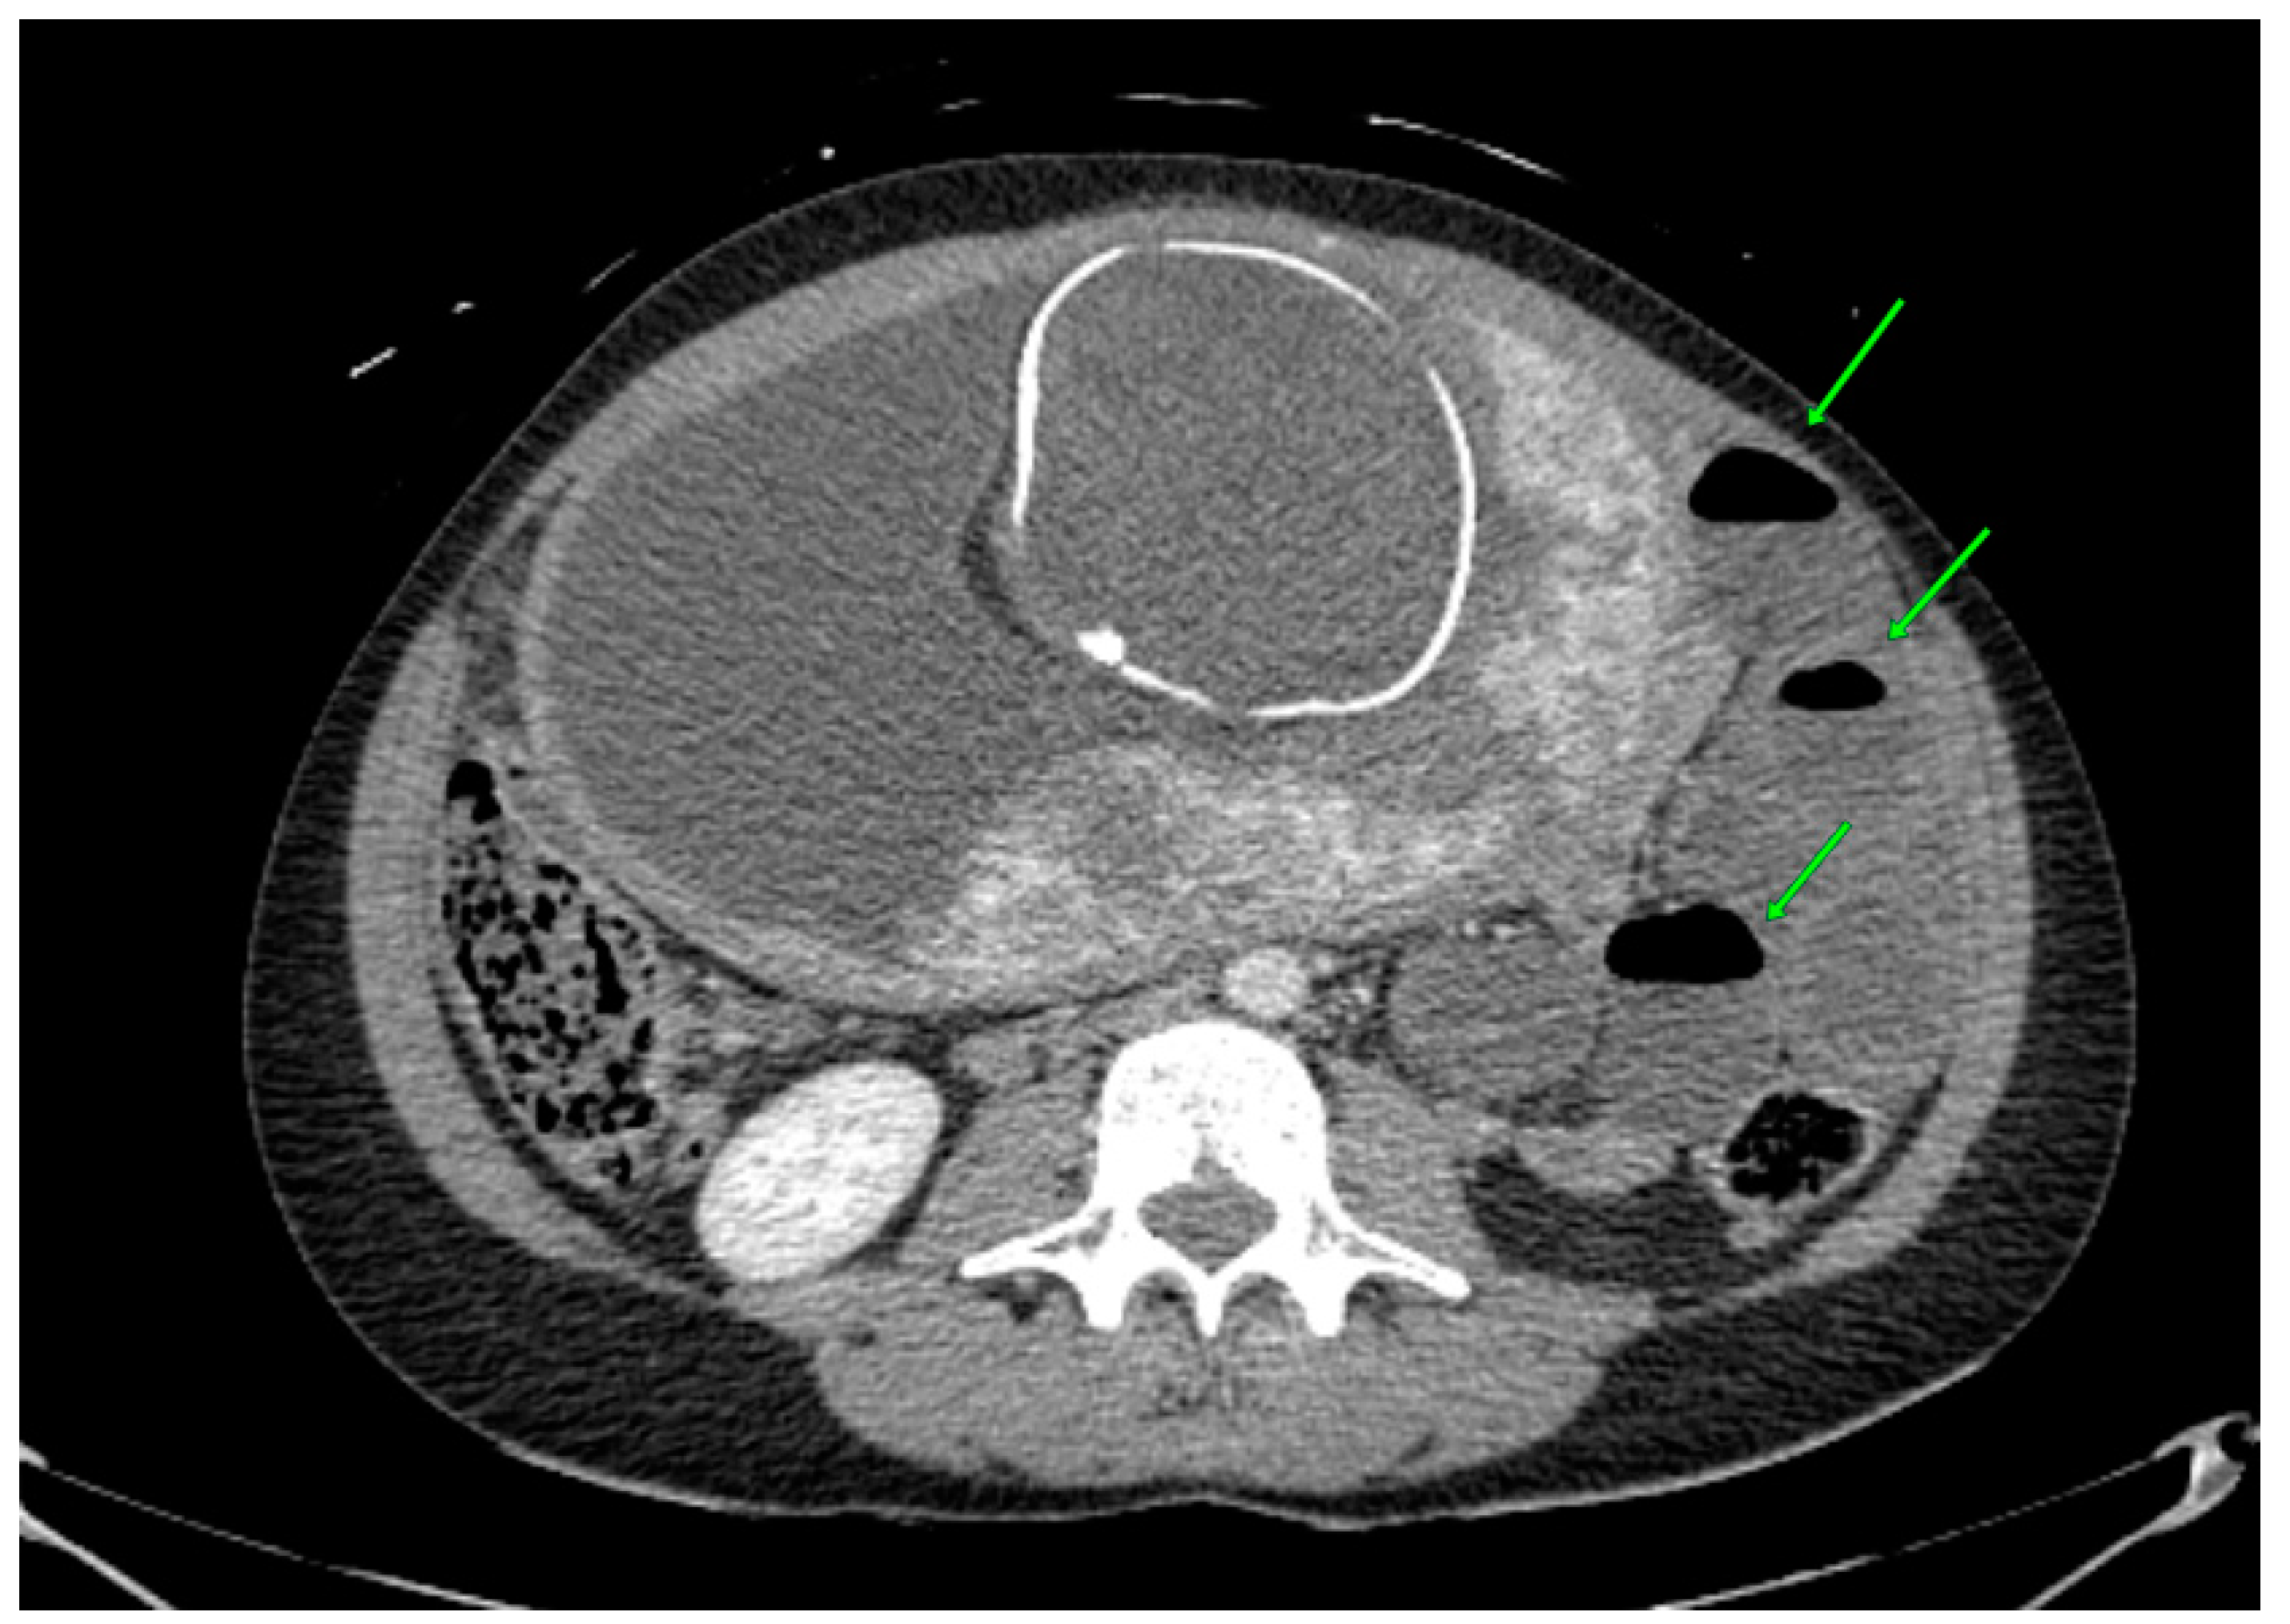

| Nagata et al. [23] | 2019 | 31 | 15 | CT 3 scan (dilated small bowel loops with multiple air–fluid levels) | Emergency laparotomy | Gastroenteritis | Gangrenous Meckel’s diverticulum |

| Yantao He et al. [26] | 2023 | 23 | 22 | US (not informative), CT scan (left lower abdominal part of the small intestine in a vortex shape, local intestinal lumen dilated) | Exploratory laparotomy and small-bowel resection | Acute gastroenteritis and preterm labor | Meckel’s diverticulum, with a 360° twist and local necrosis without perforation |